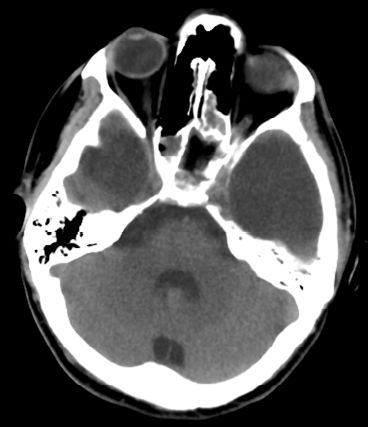

25岁男性患者,有双侧颞部蛛网膜囊肿,因醉驾而发生车祸。入院时GCS评分为15分,体格检查未见阳性体征;头颅CT和MRI提示双侧颞部蛛网膜囊肿的前端各有一颞部硬膜外血肿。左颞蛛网膜囊肿为4.8×5.4cm,右颞囊肿为3.1×3.7cm。左侧颞部EDH最大厚度3cm,右侧2.2cm;同时伴有横向的颞骨骨折(图1)。给予患者保守治疗。随后的CT复查显示EDH稳定(图2)。出院后3周,复查头颅CT显示,EDH明显吸收(图3)。

图2. 头颅CT复查。